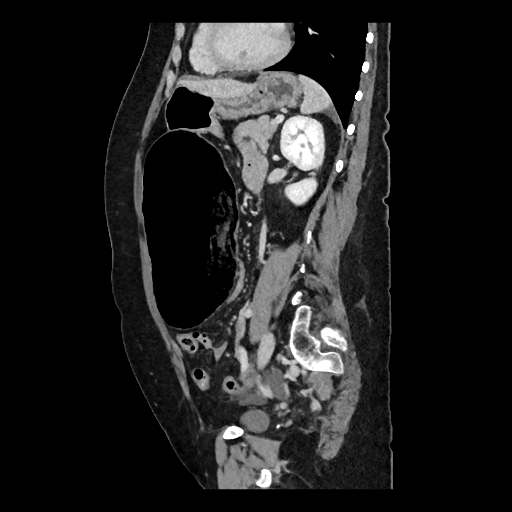

Une patiente de 59 ans, avec antécédents de lithiases vésiculaires, se présente aux urgences pour une douleur abdominale diffuse à type de colique, d'apparition brutale depuis la veille au soir. La douleur est d'intensité 8/10, sans position antalgique ni caractère transfixiant. La patiente signale que ces douleurs sont similaires à ses épisodes antérieurs de migration lithiasique biliaire. Le tableau clinique est également marqué par des nausées, six vomissements liquidiens et un vomissement biliaire à l'admission. La patiente note une inappétence ainsi qu'un épisode de selles liquides la veille. Ses antécédents chirurgicaux se limitent à une césarienne. A l'examen, la patiente est très inconfortable sans position antalgique, et afébrile (36,7°C). Les constantes vitales sont stables (TA 100/71 mm Hg, FC 83 bpm, FR 16 cycles/min, SpO2 95%). L'abdomen est souple, sensible en sus-pubien et épigastrique avec masse palpable sans défense ni détente. Les signes de Murphy et du psoas sont négatifs. Le bilan biologique révèle une légère hyperleucocytose (11,4 G/L) et une CRP à 6,8 mg/L, avec tests hépatiques normaux et des lactates à 1,2 mmol/L.